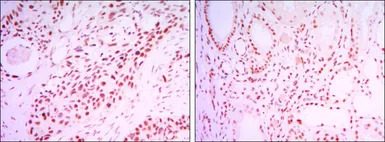

IHC-P analysis of lung cancer tissue (left) and kidney cancer tissue (right) using GTX82793 SIRT1 antibody [1F3].